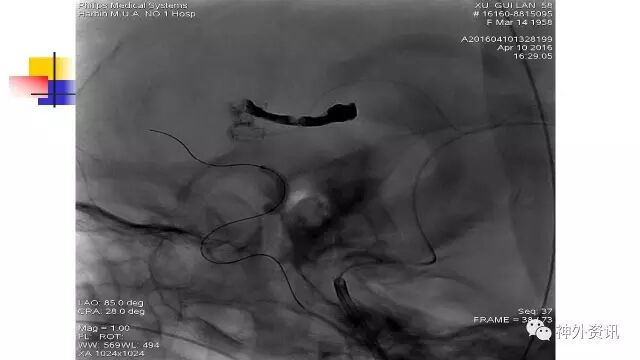

斜位动态